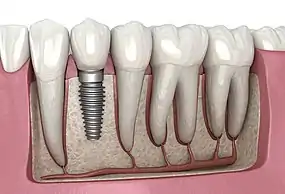

![]() A titanium dental implant with a crown attached used for a single tooth replacement | |

A dental implant (also known as an endosseous implant or fixture) is a prosthesis that interfaces with the bone of the jaw or skull to support a dental prosthesis such as a crown, bridge, denture, or facial prosthesis or to act as an orthodontic anchor. The basis for modern dental implants is a biological process called osseointegration, in which materials such as titanium or zirconia form an intimate bond to the bone. The implant fixture is first placed so that it is likely to osseointegrate, then a dental prosthetic is added. A variable amount of healing time is required for osseointegration before either the dental prosthetic (a tooth, bridge, or denture) is attached to the implant or an abutment is placed which will hold a dental prosthetic/crown.

Single tooth implant restoration

Single tooth restorations are individual freestanding units not connected to other teeth or implants, used to replace missing individual teeth.[11] For individual tooth replacement, an implant abutment is first secured to the implant with an abutment screw. A crown (the dental prosthesis) is then connected to the abutment with dental cement, a small screw, or fused with the abutment as one piece during fabrication.[15]: 211–232 Dental implants, in the same way, can also be used to retain a multiple tooth dental prosthesis either in the form of a fixed bridge or removable dentures.